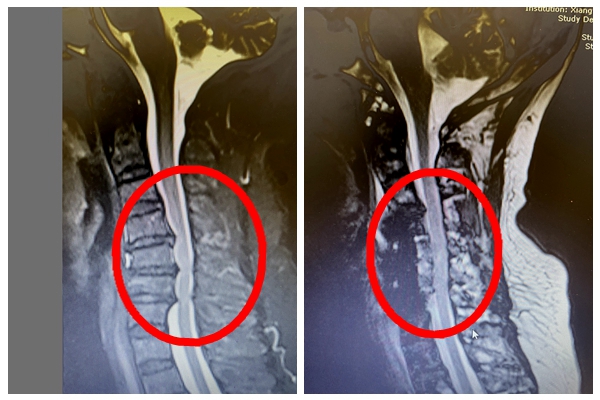

手术前后对比图

2月22日,由张朝跃教授、陈芳田副主任医师、刘磊主治医师、向思宇医师组成的手术团队为患者实施了颈前路颈5、6椎体次全切、椎管减压、人工椎体置入、钉板系统内固定术。

手术很顺利,术后返回病房患者便感觉四肢麻木乏力感明显改善,双手也能正常握拳。为促进患者的早期康复,经过骨科医师及张娟护士长带领的护理团队悉心照料和康复指导,为患者设计了早期个性化康复方案。术后复查CT及核磁共振:椎管扩大、脊髓受压解除。目前患者已经在头颈胸支具保护下顺利下床活动。